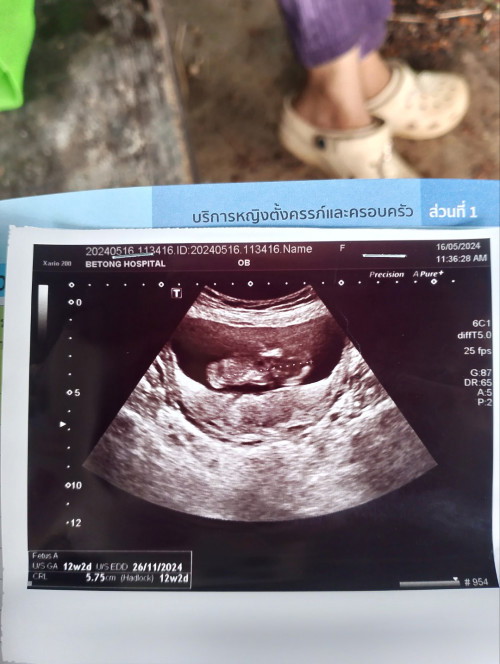

ภาพแรกของเบบี้G4💓💓12w+4ตอนนี้14+3แล้วจร้าาา

ซาวด์12W ตอนนี้19W กำหนดคลอด5 พฤษจิกายน 2567😍